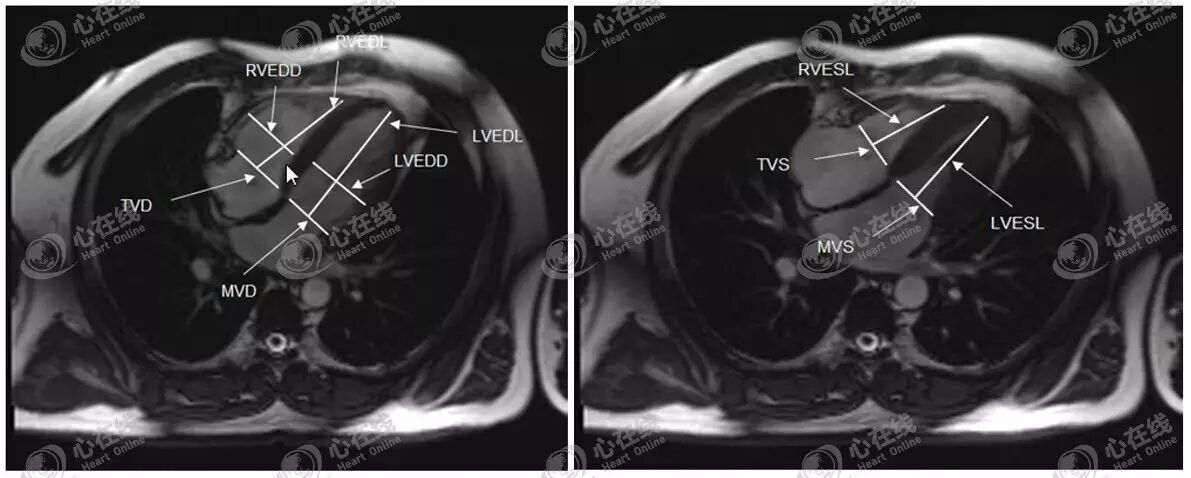

6、四腔心平面各房室径线的测量

如图12左图,在TrueFISP序列标准心室长轴舒张末四腔心平面,可测量舒张末三尖瓣口径(TVD)、二尖瓣口径(MVD)、左室长轴径(LVEDL)、右室长轴径(RVEDL)、左室短轴径(LVEDD)、右室短轴径(RVEDD)。

如图12右图,在TrueFISP序列标准心室长轴收缩末四腔心平面,可测量收缩末三尖瓣口径(TVS)、二尖瓣口径(MVS)、左室长轴径(LVESL)、右室长轴径(RVESL)。

图12